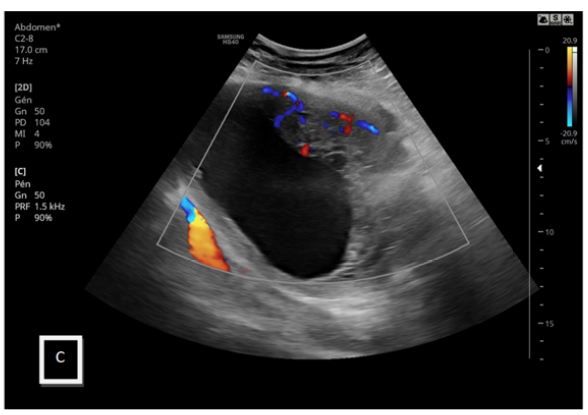

Large Uterine Fibroids with Cystic and Malignant Degenerative Changes Mimicking Ovarian Carcinoma: A Rare Case Report

Khadija Laasri, Kaouthar Sfar, Yahya El Harras, Nazik Allali, Siham El Haddad and Latifa Chat. 12(5): 01-07.